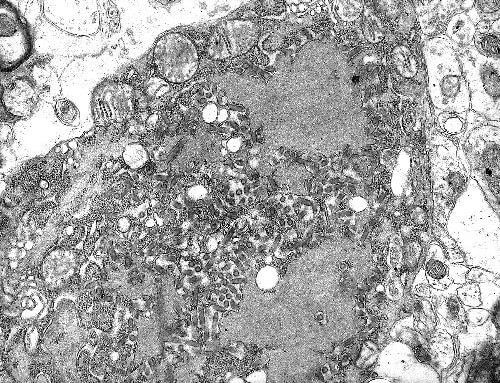

اگرچه ظهور واکسن هاری برای حیوانات اهلی در دهه 1920، وقوع بسیار نادر این بیماری در کشورهای توسعه یافته را در پی داشته است، اما این بیماری در هند و بخش هایی از آفریقا همچنان یک مشکل جدی بشمار می آید. طبق اظهارات مالبرگر، “این ویروس به مغز آسیب می رساند، و بیماری واقعاً بدی است.” وی گفت: “ما واكسن هاری را داریم و آنتی بادی هایی داریم كه ضد هاری عمل می كنند، بنابراین اگر كسی مورد گزش حیوان هاری قرار گیرد قادر به درمان این فرد هستیم.” با این حال وی اظهار داشت “در صورت عدم درمان، احتمال وقوع صد درصدی مرگ قطعی است.”